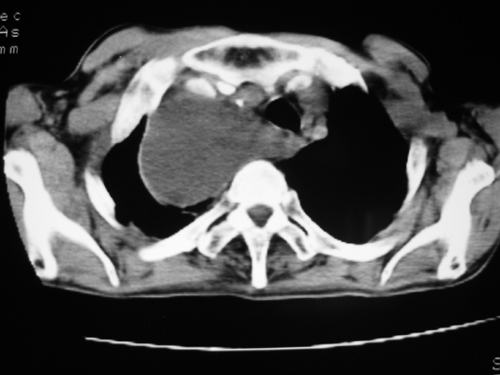

以下是引用yangyudong333在2008-4-29 5:46:00的发言:[br]1左上叶结节呈分叶状,边缘毛刺,考虑肺癌并纵隔淋巴结转移可能性大,结核待排,[br] [br]2右侧多发包裹性胸腔积液